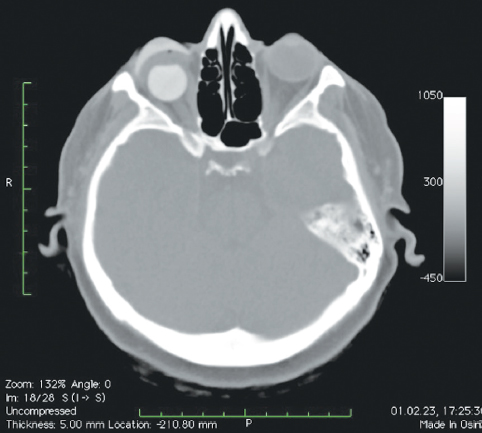

Рис. 10. Пациентка, 42 года. Состояние после операции с использованием имплантата с изменённой геометрией (a) и множественными фрагментами из такого же материала в тканях орбиты (b, показано стрелками)

Fig. 10. Patient, 42 y. o. The state after surgery using an implant with modified geometry (a), and multiple fragments of the same material in the tissues of the orbit (b, shown by arrows)

В мягких тканях вокруг изменённых имплантированных сфер нами выявлены уплотнения, без признаков кальцинации и деструкции стенок орбиты (рис. 7, 8). Кроме того, у одной пациентки было отмечено не только изменение геометрии сферы в виде срезанной части (рис. 10, а), но и наличие множества фрагментов полимерного материала идентичной рентгенологической плотности. Эти фрагменты имплантата находились за задним полюсом полимерного вкладыша в мягких тканях до вершины орбиты (рис. 10, b).

Во-вторых, сам имплантат приобретает другие биомеханические характеристики после изменения геометрии и может смещаться в тканях глазницы в процессе формирования капсулы в условиях постоянного движения культи, особенно после энуклеации (рис. 10, b).